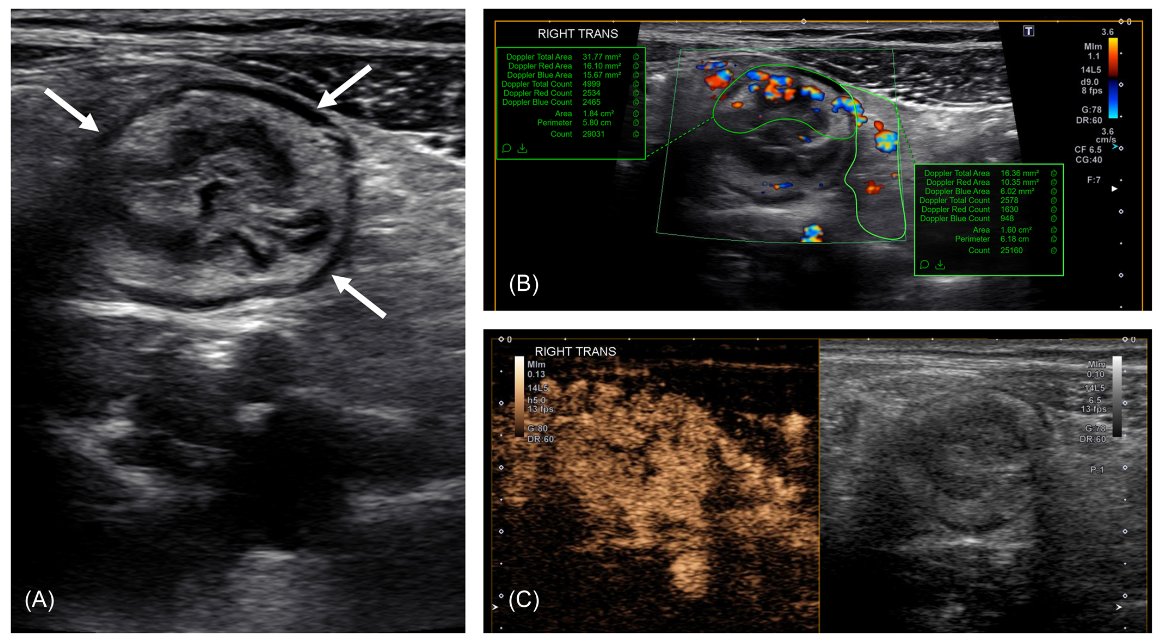

Time to move intestinal #ultrasound Doppler blood flow assessments from qualitative to quantitative in #Crohns - we can likely do better by measuring vessel density ⬇️ @CincyKidsRad @MotilentNews @JPGNonline https://t.co/XLL2mAawQW